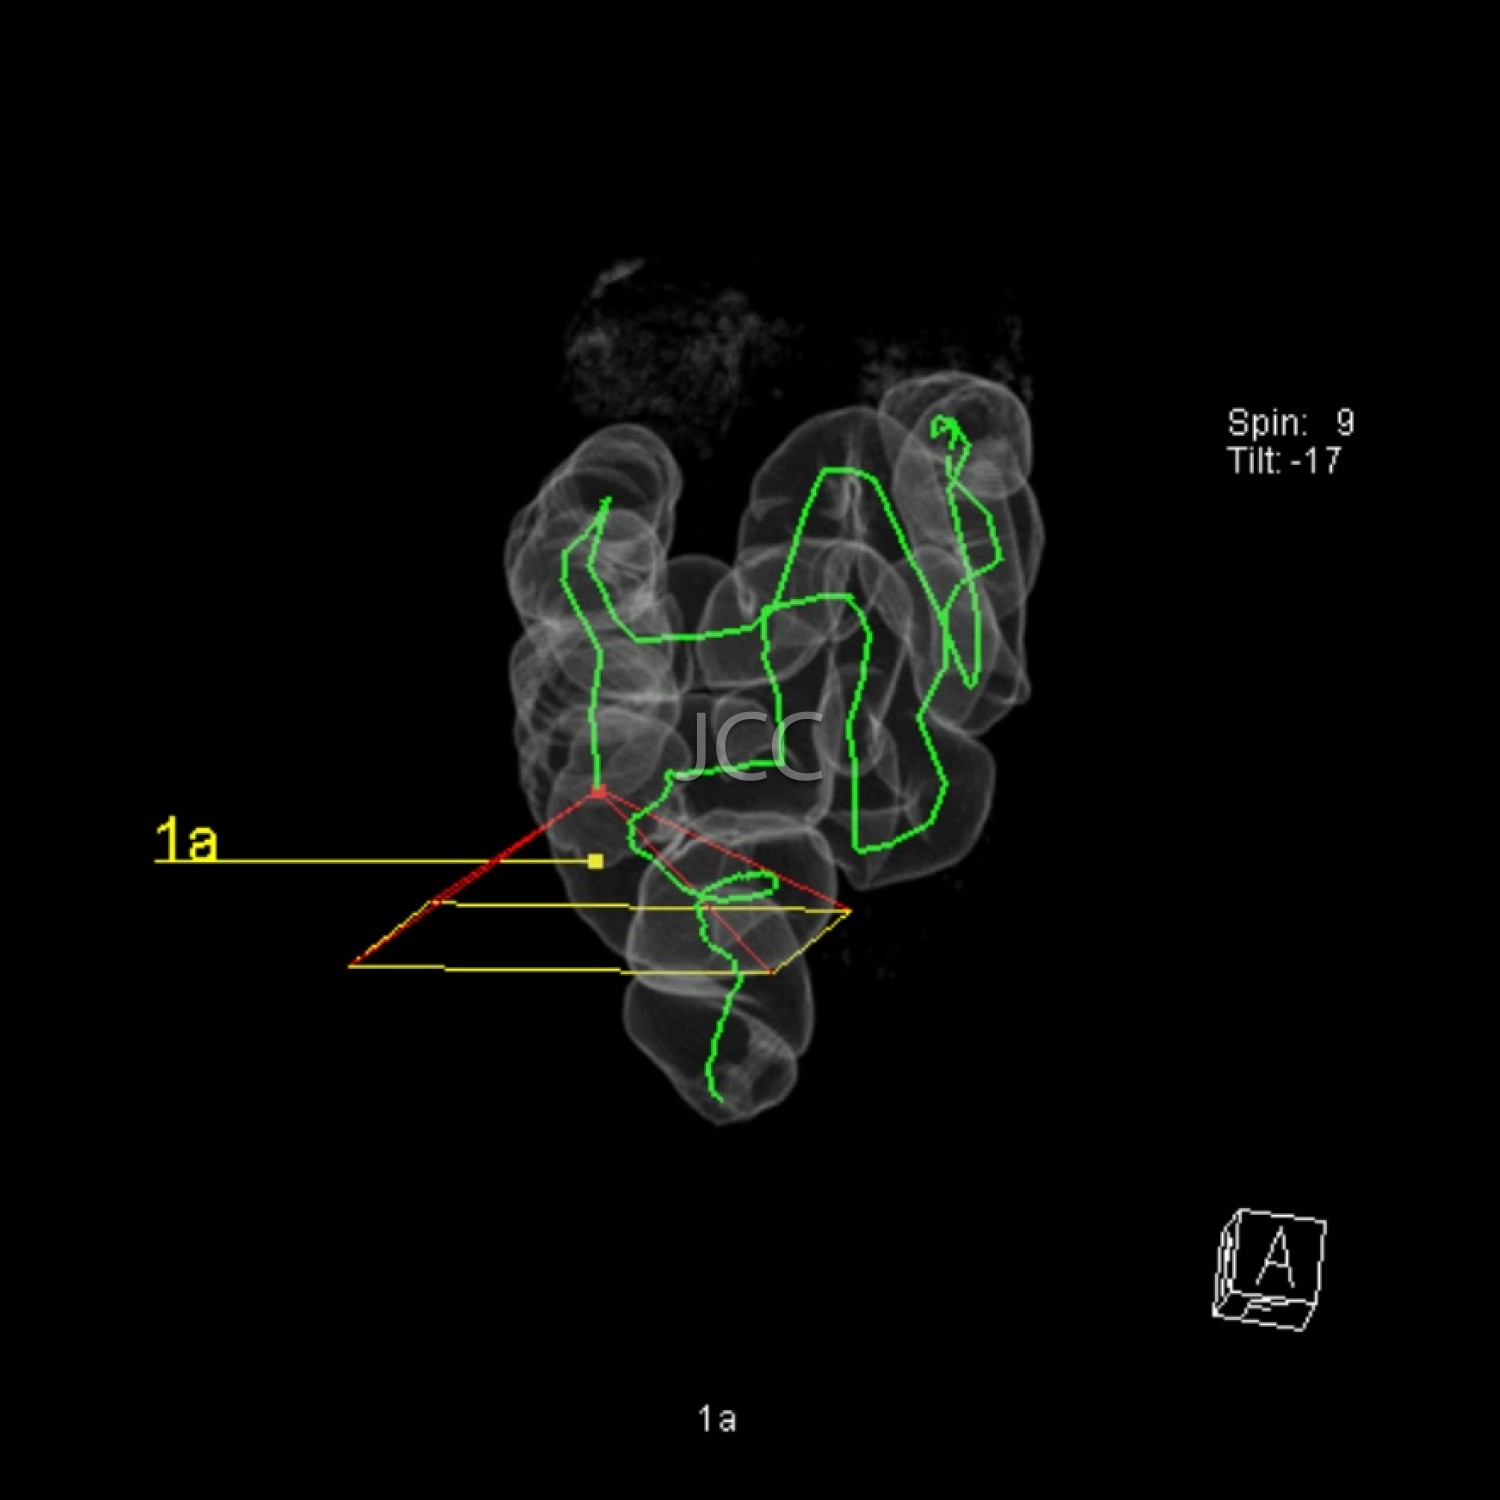

Pela 1ª vez na história da medicina, através da tecnologia multi-detector, com dupla ampola e ressonância magnética de última geração 3 tesla, é possível, de modo não invasivo e capacidade diagnóstica comprovada, efectuar o screening de processos patológicos, para prevenção de doença cardíaca, neoplasias e acidente vascular cerebral – AVC. Salienta-se que com o nosso equipamento de TAC dual source - 256 cortes -  a dose de radiação é  muito baixa (cerca de 10 vezes inferior à dose dos equipamenos de TAC de 64 cortes).  Os dados obtidos nestes equipamentos de ultima geração são tratados em estações de trabalho de alto nível, que utilizando sistemas CAD e de visualização tridimensional, resulta em informação detalhada e muito rigorosa.

O conjunto destes exames com este tipo de equipamento constitui a modalidade de escolha para o estudo imagiológico do corpo humano, através de angiografia não invasiva do coração, do cérebro e dos vasos do pescoço, colonoscopia virtual por TAC assim como a avaliação dos restantes orgãos e estruturas ósseas do tórax, do abdomen e da pélvis, o estudo da próstata no caso do homem e da mama no caso da mulher.

• Colonoscopia virtual por TC